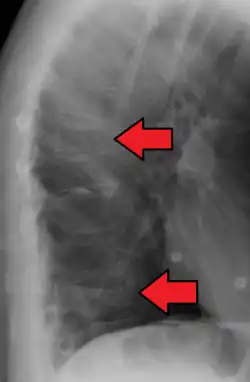

Compression fracture of T12